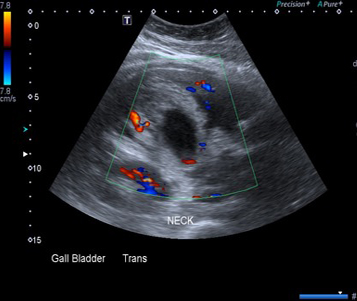

Image echographique de

cholecystite aigue lithiasique : Vesicule est

distendue , paroi epais , image de calcul

multiple au ventre de la vesicule biliaire |